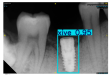

| Image Resolution = 825 × 1200 | ||||

|---|---|---|---|---|

| Test Image 1–4 | ![]() | ![]() | ![]() | ![]() |

| Accuracy | 94.13% | 95.29% | 92.88% | 91.80% |

| Recall | 96.71% | 94.03% | 93.88% | 92.15% |

| Model reference time | 6.57 ms | 7.08 ms | 7.12 ms | 6.43 ms |

| Dentists’ average diagnostic time | 2.78 s | 4.55 s | 7.78 s | 7.23 s |